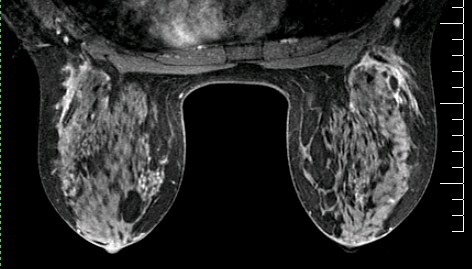

Figure 2. Ripple-like artifact in sagittal reformat from axial source scan data